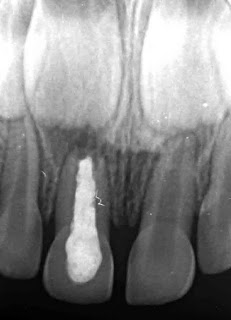

El procedimiento como en la imagen consiste en retirar el tejido solamente de la cámara pulpar, evaluar la condición del tejido pulpar radicular, colocar un acondicionador pulpar ( MTA, formocresol o sulfato ferrico ) y colocar material de curacion temporal ( oxido de cin ) y en una cita postrior colocar una corona dental molar.

Radiograficamente se puede ver el relleno de la camara pulpar con cemento de oxido de cinc y la corona ajustada sobre el molar temporal del niño. Mas abajo de este diente observamos el germen del premolar que en un futuro erupcionará un lugar de esta molar temporal.